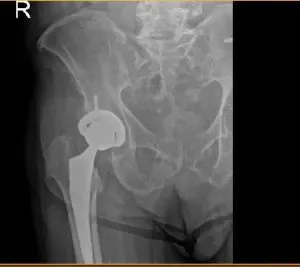

Post op hip X-ray

The patient underwent a right total hip arthroplasty, A curved incision centered over the greater trochanter was used for the arthrotomy. Skin and subcutaneous tissues were incised. Fascia was then divided. The hip was placed into internal rotation and the posterior soft tissue structures were then taken down and tagged for future repair.

The hip was then dislocated. The lesser trochanter to the center measurement was taken and the neck resection was made at the correct level. Head was then removed. Attention was then turned towards the acetabulum.

The remainder of the labrum was then debrided. The acetabulum was sequentially reamed. The final shell was then placed into position in the correct abduction and anteversion. Screw was used for additional fixation. Additional osteophytes were then removed.

The poly was placed over the shell. Attention was turned towards the femur and the femur was sequentially broached. The final broach was left into position. The head was then placed over the trunnion. Hip was then relocated and trialed through a full physiological range of motion. The hip was stable in all physiological range of motion. Hip was then dislocated.

The combined anteversion was correct. The hip was then dislocated. The trial components were removed. Final components were then placed into position.

Post-operative films show Right hip total arthroplasty, in good alignment, mild sacroiliac degenerative changes. Patient returned for a post operative appointment for staple removal and patients prognosis is good, due to an uncomplicated surgery. Patient is compliant with the outpatient physical therapy program, and is weight bearing fully bilaterally.